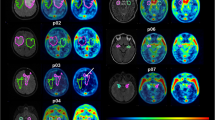

[18F]AVT-011 is a substrate of mouse ABCB1A/B and ABCG2

To determine whether [18F]AVT-011 is a substrate of mouse ABCB1 and/or ABCG2, we assessed its uptake in the brains of wild-type and transgenic mice lacking either transporter (Fig. 2a). The brain was selected as the region to assess selectivity because both transporters are co-expressed at the blood-brain barrier and prevent substrate entry into the brain. The uptake of [18F]AVT-011 in brain peaked within the first 5 min before reaching a plateau for the remaining scan time (Fig. 2b). Brain uptake (area under the curve, AUC5–120 min) of [18F]AVT-011 was 2-fold higher in Abcb1a/b−/− mice (Padj < 0.01) than in wild-type mice but was not increased in Abcg2−/− mice (Padj = 0.14) (Table 1). After pretreatment with tariquidar (15 mg/kg), brain uptake of [18F]AVT-011 increased 3-fold in wild-type mice (Padj < 0.001) and 8-fold in Abcg2−/− mice (Padj < 0.001), relative to baseline values. However, uptake did not significantly increase in Abcb1a/b−/− mice after inhibition (Padj = 0.78; Fig. 2c and Table 1).

[18F]AVT-011 is a substrate of mouse ABCB1 and ABCG2, as assessed by PET imaging. a Representative summation images of radiotracer uptake in the brain (% injected dose, (ID)/g) after intravenous injection of [18F]AVT-011 in wild-type or transgenic mice lacking Abcb1a/b or Abcg2. b Time-activity curves in all strains of mice at baseline conditions and c after pharmacological inhibition of ABCB1 with 15 mg/kg tariquidar (TQR). Symbols represent mean ± SD from n = 5 mice/strain, with the exception of Abcg2−/− after inhibition (n = 2). Inset shows time-activity curve ranging from 0 to 1 %ID/g

To measure ABCB1 function in chemotherapy-resistant tumors, we imaged three groups of mice with [18F]AVT-011 before and after tariquidar treatment (Fig. 3a, b) and with [18F]FDG for anatomical localization. Wild-type mice were implanted orthotopically with breast tumors comprising three levels of Abcb1a/b expression and ABCB1 protein levels (Supplemental Fig. 2) found in clinical tumors [1]: basal, intermediate (3-fold increase in Abcb1a/b), or high (~ 521-fold increase in Abcb1a/b). These tumor grafts were derived from Brca1−/−;p53−/− mouse breast tumors that were previously responsive to chemotherapy (basal) or developed resistance after several cycles of treatment with doxorubicin (intermediate) or with pegylated liposomal doxorubicin [26]. After injection of [18F]AVT-011, radioactivity concentrations (%ID/g) in tumors peaked within the first 5 min and reached a plateau by 45 min (Fig. 3c, d). Tumor uptake of [18F]AVT-011, measured as AUC of %ID/g*min from 5–42.5 min, was 15% lower in the intermediate group (Padj = 0.10) and 32% lower in the high ABCB1–expressing group (P < 0.001) than in the basal group (Fig. 4a). In contrast, tumor uptake of [18F]FDG, measured as %ID/g at 60 min after injection, was not significantly different among the three groups (intermediate vs basal, Padj = 0.92; high vs basal, Padj = 0.16; Fig. 4b).

[18F]AVT-011 can detect ABCB1 function in an orthotopic mouse model of breast cancer, as assessed by PET imaging. a Schematic of dynamic PET study performed in tumor-bearing mice. b Summation PET images of [18F]AVT-011 from 0 to 45 min (baseline) and from 45 to 90 min (tariquidar, TQR) after radiotracer injection in basal and high ABCB1–expressing tumor groups. Color bar represents radioactivity concentration (%ID/g), set from 0.2 to 2. Anatomical structures are highlighted with white broken lines and labeled with arrows. c Time-activity curves in tumors expressing basal, intermediate, and high levels of ABCB1. Tariquidar (TQR, 15 mg/kg) was injected intravenously at 45 min. Symbols represent mean ± SD from n = 6 mice (basal tumors), n = 7 mice (intermediate-ABCB1 tumors), and n = 5 (high-ABCB1 tumors). d Time-activity curves in tumors expressing basal and high levels of ABCB1 not treated with tariquidar. Symbols represent mean ± SD from n = 3 mice (basal tumors) and n = 5 mice (high-ABCB1 tumors)